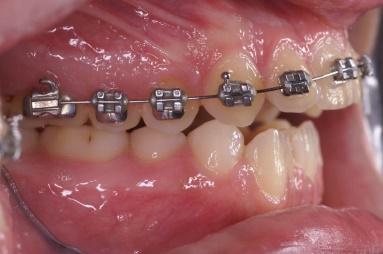

Les arcs orthodontiques

Les arcs orthodontiques moteur de l’appareillage sont au début du traitement de faible diamètre et très élastiques délivrant des forces légères, le matériau est le titane . Les diamètres des fils et leur rigidité augmentent dans les phases suivantes . Le fil est change une fois qu’il a délivré son action , les progrès en metallo-technie permettent de laisser les fils orthodontiques plus longtemps sans perte d’efficacité .

Bagues auto-ligaturantes

Les bagues sont maintenant auto-ligaturantes, il n’existe plus de ligature ( lien bloquant le fil orthodontique dans la rainure de la bague) l’avantage est pratique pour le praticien et moins de gène et une meilleure hygiène pour le patient.